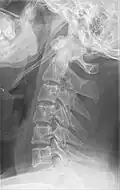

![]() Vistas lateral y anteroposterior de una radiografía cervical que muestra osificación del ligamento estilohioideo. | ||

La apófisis alargada o calcificación del ligamento estilohioideo suelen mostrarse fácilmente a través de una prueba radiográfica. De forma adicional se puede realizar un TAC para confirmar el diagnóstico y ver qué estructuras están siendo afectadas.[10]